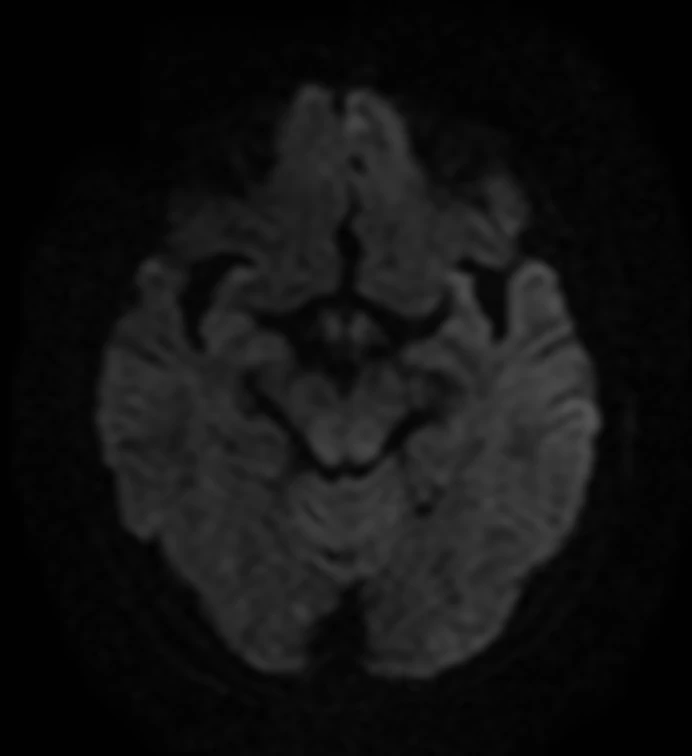

Женщина 32 года. Больной считает себя с 2024 г, когда стала отмечать онемение угла рта. Со слов пациентки ей был предварительно выставлен диагноз - РС, но дополнительных методов обследования и специфического лечения не проводилось. В настоящее время жалоб нет. В исследовании от октября 2024 отмечался очаг в левой затылочной доле с выраженным контрастированием, в настоящее время этот же очаг отмечается с сохраняющимся контрастированием. Формально - есть выполнение критериев диссеминации и в пространстве (юкстакортикальный и перивентрикулярный очаги есть), и во времени (есть усиливающиеся и неусиливающиеся очаги), клиника тоже вполне укладывается. Но! Найти в литературе подобных случаев мне не удалось, видел сам и максимум, что находил в литературе - полгода контрастирования. Получается, мы имеем дело с крайне атипичным рассеянным склерозом, или это не рассеянный склероз. А тогда что? Сосудистая мальформация не вариант - на SWI не видать. Какая-то ганглиоглиома? А другие очаги тогда что? Есть соображения? Кстати, диффузия стойко повышенная, и на б1000 почти не видно (изо). На Т2 не меняется